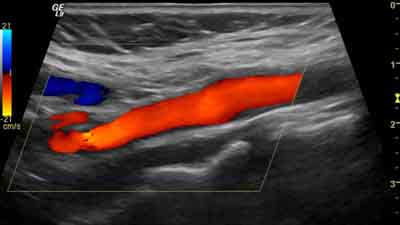

- les fistules artério-veineuses d’hémodialyse : bilan pré-création, suivi